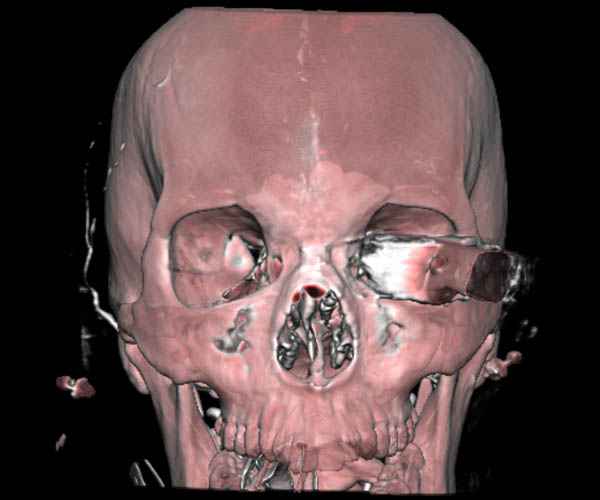

По протоколу сделаны все необходимые исследования: рентген, ангиограмма с 3Д реконструкцией, где обнаружили что все жизненно важные сосуды не задеты, даже некоторые "сидят" изгибаясь на ноже.

Одним махом нож удалить не удалось, пришлось раскачать и потом двумя руками удалили нож. Рана без кровотечения, обработана и зашита.